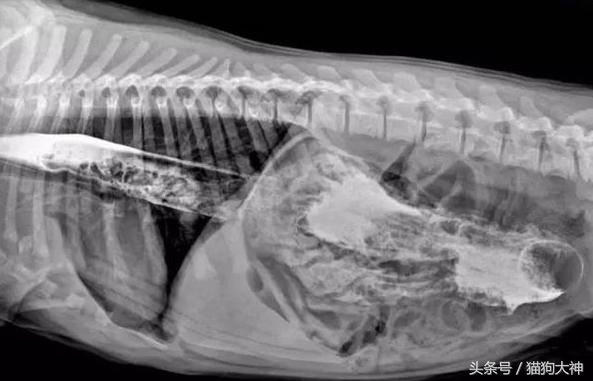

但狗狗傻起来简直让人目瞪口呆,这只狗狗竟然吞下了一把这么长的刀!不是所有狗狗都有能化险为夷的好运气,所以就需要主人留心帮它们排除生活在可能存在的危险。

竟然是一根这么长的挠痒痒拍!!!比起表演吞剑的杂技高手,这只狗子简直超神!